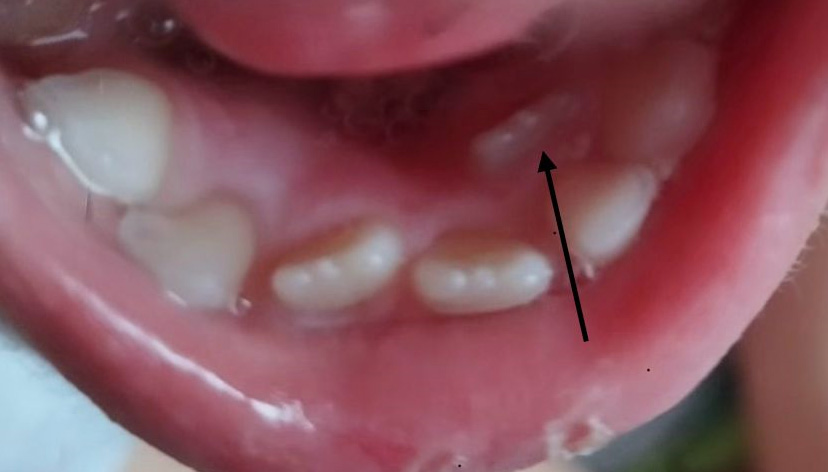

- Нарушение гигиены – по этой причине возможно образование кариеса на новом постоянном зубе. (фото 3)

- Неправильный прикус – из-за деформации зубных рядов.

- Тщательно следить за гигиеной полости рта, дочищать скученные зубки монопучковой щеткой и зубной нитью.